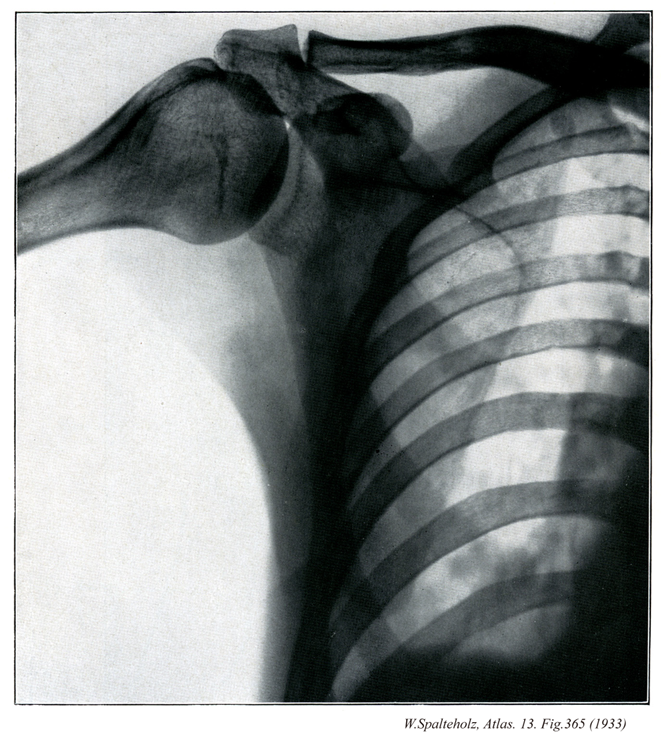

365_00【Pectoral girdle; Shoulder girdle上肢帯;胸帯;肩帯 Cingulum pectorale; Cingulum membri superioris】 Its skeletal framework consists of the scapulae and the clavicles.

→(上肢帯とは肩(肩甲部)に相当し、体幹と上腕とを結合する役目をする(骨では鎖骨と肩甲骨が上肢帯骨である)。上腕と体幹との移行部で肩関節を包んでいる範囲を肩というが、その広がりははっきり規定されていない。)